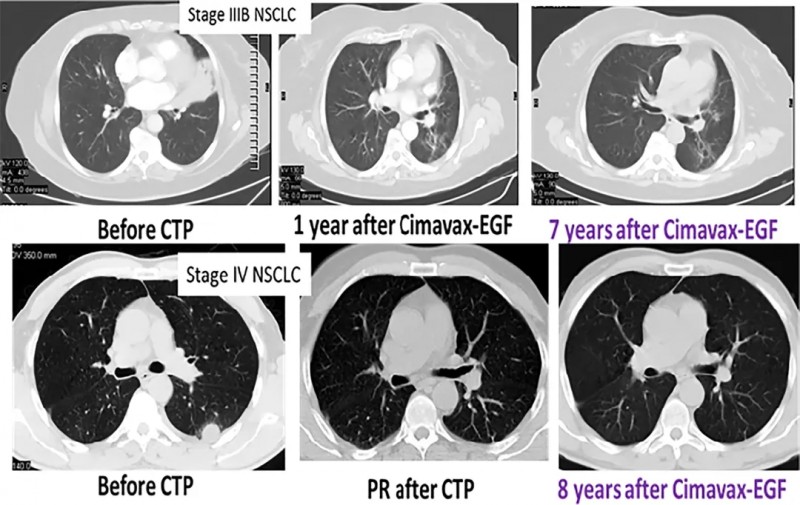

03、Cimavax肺癌疫苗为肺癌患者开启长生存之门

肺癌疫苗CIMAvax-EGF是由古巴分子免疫学中心经过25年,穷尽了第一代科学家的心血成功自主研发的全球首个注册的用于晚期非小细胞肺癌的治疗性疫苗,原本是迫于美国全面封锁的就医压力,自主研发的疫苗,自给自足就够了,没想到一问世引起了全世界的轰动。目前这款疫苗已经在古巴,秘鲁,白俄罗斯等全球多个国家获批上市。

近期,古巴公布了针对晚期 NSCLC 患者的 CIMAvax-EGF IV 期临床试验,这项真实世界试验表明,大约 20% 的患者接种疫苗超过 1 年或更长时间,值得注意的是,44 名患者在 3 年或更长时间后仍接种疫苗!

2位幸运的晚期肺癌患者接受疫苗治疗后,病情得到长期控制,截至文献发表时,已达到7年和8年,CIMAvax-EGF疫苗已经为众多晚期肺癌患者开启长生存之门。

好消息是,国内已有众多肺癌患者通过医学部向古巴医疗部门申请肺癌疫苗,配合标准治疗延长生存期,提高生活质量!